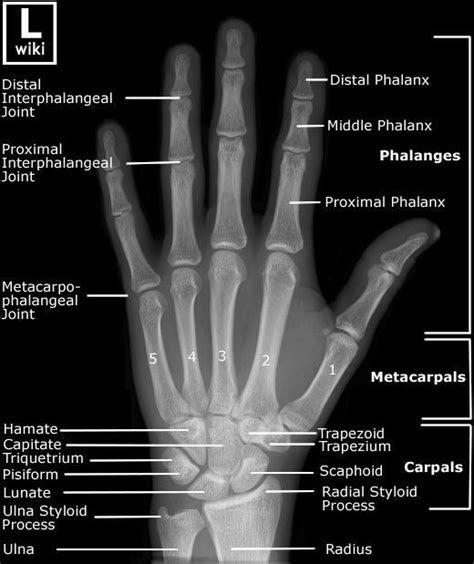

How To Read X Rays Of Bones

How To Read X Rays Of Bones. One is high energy and the. Aleem lalani, an orthopedic surgeon at the university of.